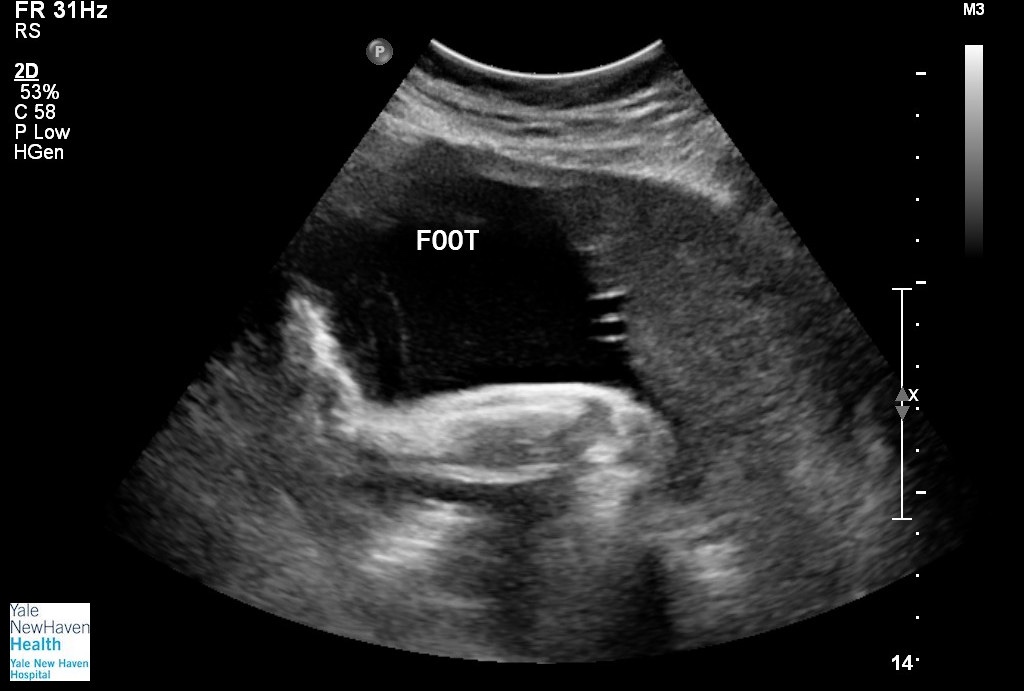

It was a whirlwind from there. We decided to keep the news to ourselves because I didn’t want anyone to know until I felt that the baby was viable (about 12 weeks). It took some convincing for me to believe that it was even really happening. I got to see Georgia for the first time when I was 9 weeks pregnant. I went to the ER with a kidney stone and they decided to check and make sure the baby was okay. It was then that I got to see her heartbeat and was able to fully accept that I was pregnant.

A lot of different things were happening around the 18 week mark. The doctors informed us that the baby was measuring small. She was a few weeks behind in growth (but developmentally on par with 18 weeks as far as they could tell). We didn’t think much of it because everything else was going so well with her. On July 4th, 2019 I felt her kick for the first time. It brought such comfort and peace. All the while, I was silently suffering with Perinatal Depression (blog post coming next week).

The day after I reached 30 weeks, I went to a high risk appointment. That appointment changed everything. They checked on the baby and saw that she was still small, but they were okay with how she was doing. They were not however, okay with how I was doing. While I felt fine, my blood pressure was continuing to rise. The doctor there decided to send us to the hospital for observation over the weekend. So we took our time and ran home. I packed a bag with a blanket (I cannot stay anywhere without my giant fuzzy blanket) and some pajamas (there was no way I was wearing a stupid gown). Oh and I threw in some snacks because during the second trimester I learned I could stomach some snacks.